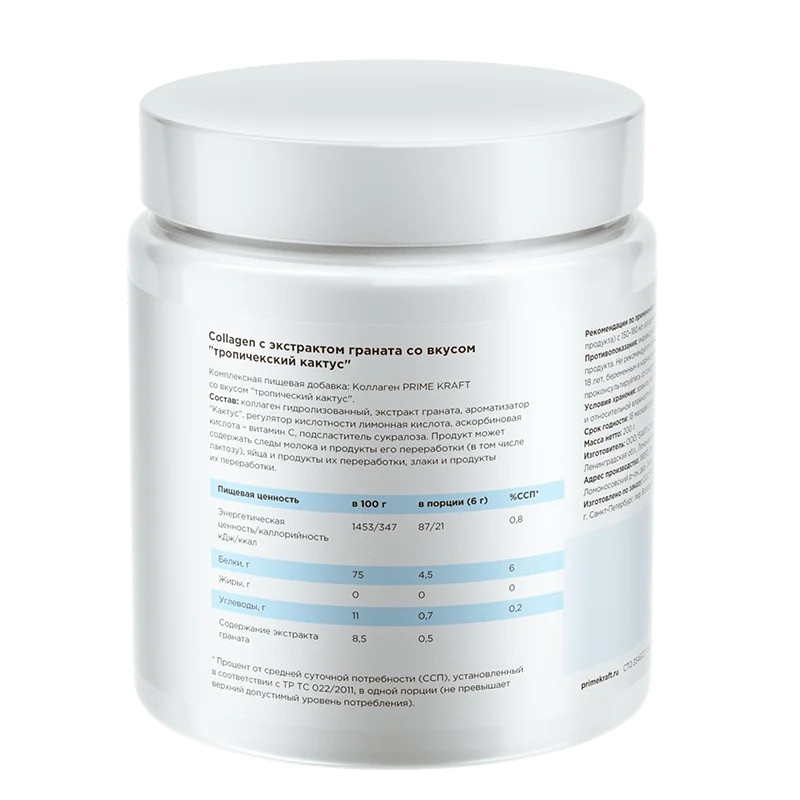

Коллаген от Prime Kraft – гидролизованный говяжий I-го типа, дополнительно обогащен витамином С, которая улучшает его усвояемость в организме, и экстрактом граната – природным антиоксидантом, который содержит удивительный набор из 15 аминокислот, причем 6 из них есть только в мясе и для растительной пищи уникальны!

Принимать коллаген от Prime Kraft рекомендуется 1 раз в день для профилактики, для активной поддержки восстановления суставов – 2 раза в день. Для этого надо смешать 1 мерную ложку (6 г сухого продукта) с 150-180 мл холодной питьевой воды в стакане или шейкере – не смешивая с приемами пищи и тем более протеином.